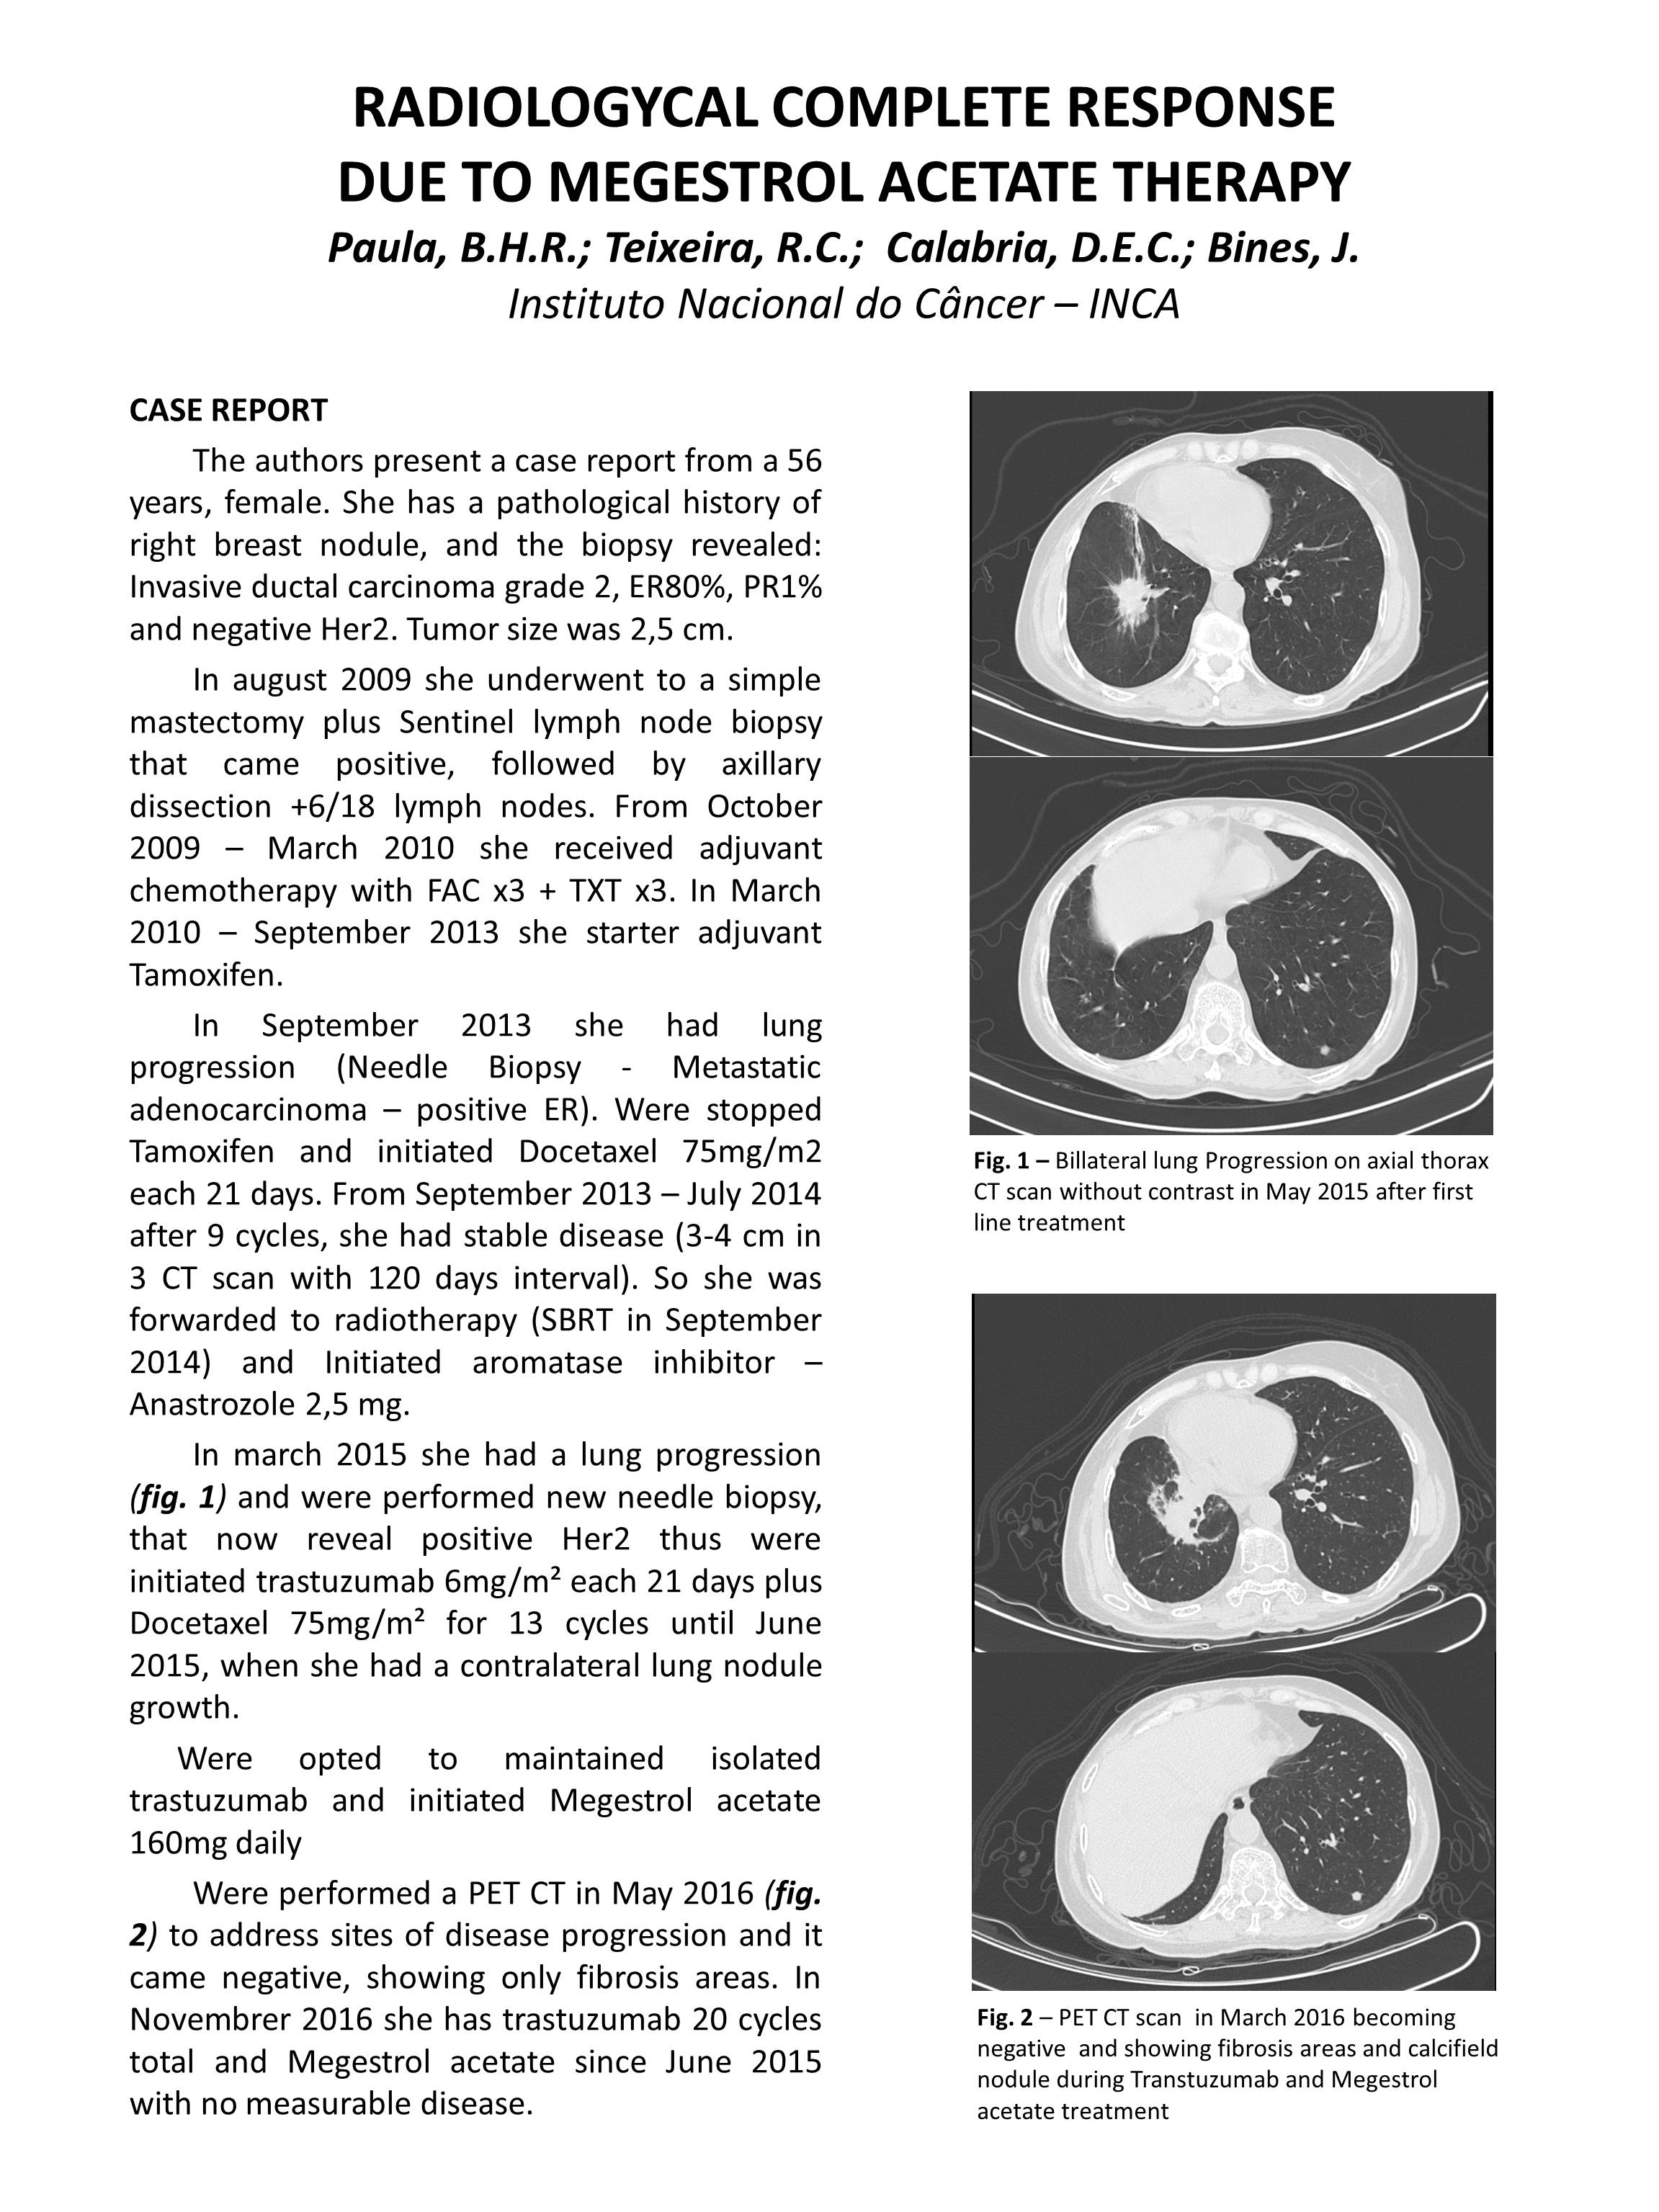

poster franco brasileiro.JPG

1 p.: il. p&b.

Acetato de Megestrol

Megestrol Acetate

Radiologia

Radiology